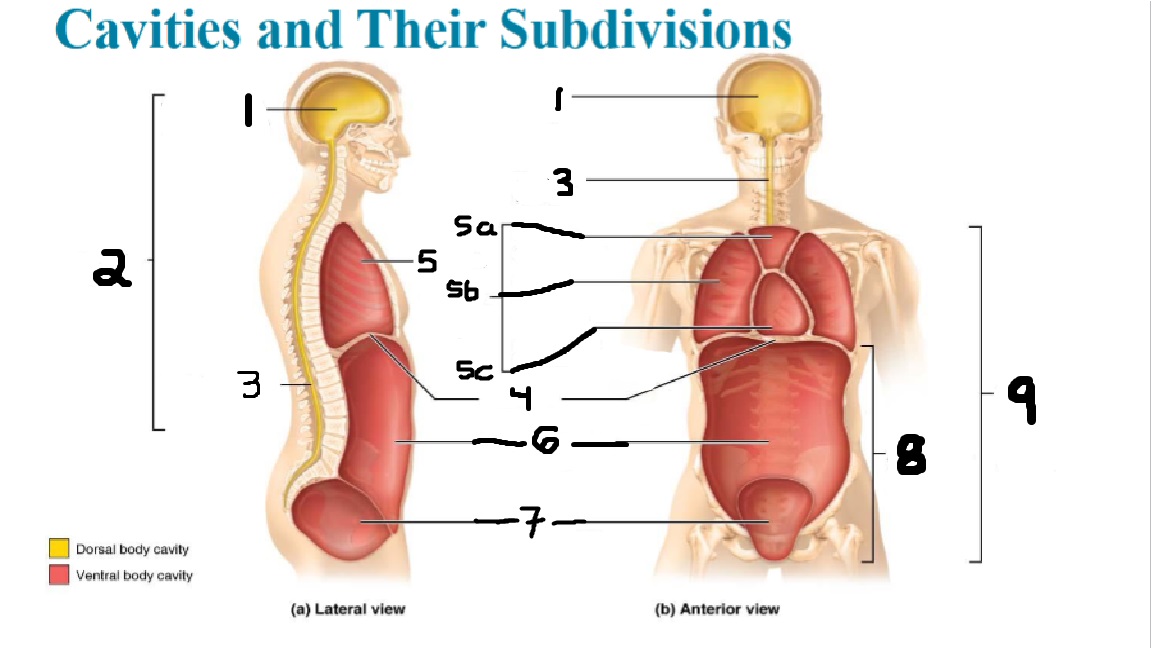

What cavities are part of the dorsal cavity?

The cranial and the Spinal (vertebral) cavities

What kind of cavity is labeled 2?

The dorsal body cavity (containing the cranial and spinal cavities)

What is the purpose of the dorsal cavity?

protects the nervous system

What is the main organ encased by the cranial cavity?

the brain

What cavity is labeled #1?

The cranial cavity

What is the main organ encased by the vertebral cavity?

the spinal cord

What is another word for the vertebral cavity?

the spinal cavity, or the spinal canal

What body cavity is labeled 3?

the vertebral cavity.

What cavities are included in the ventral cavity?

the thoracic, abdominal, and pelvic cavities.

What body cavity is labeled #6?

the abdominal cavity.

What are the main organs of the abdominal cavity?

the digestive organs such as the stomach, intestines, spleen and liver

What cavities are included in the Abdominopelvic cavity?

the abdominal cavity and the pelvic cavity

What body cavity is labeled #8?

The Abdominopelvic cavity

What does the diaphragm separate?

the thoracic and the abdominal cavities

What is labeled #4?

the diaphragm

What organs does the pelvic body cavity contain?

urinary/reproductive organs and rectum

What is labeled #7?

the pelvic cavity

What does the thoracic cavity encase?

the heart and the lungs

What is labeled #5?

the thoracic cavity

What part of the thoracic body cavity is labeled 5a?

superior mediastinum

What part of the thoracic body cavity is labeled 5b?

pleural cavity

What part of the thoracic body cavity is labeled 5c?

pericardial cavity within the mediastinum

What body cavity encloses the heart?

the pericardial cavity.